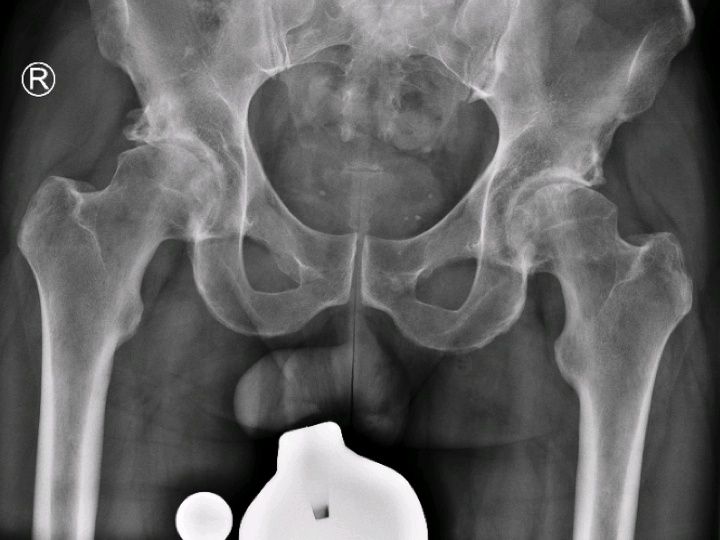

Beidseitiger Hüftgelenkersatz in nur einer Operation mit der AMIS-Technik

Patienten mit beiderseitig fortgeschrittener Hüftarthrose stehen vor besonderen Herausforderungen. Werden beide Hüftgelenke nacheinander ersetzt, so müssen die Patienten mit langen Ausfallzeiten und einer langen Rehabilitationsphase rechnen. Nach der Operation der ersten Seite kommen die Patienten häufig noch